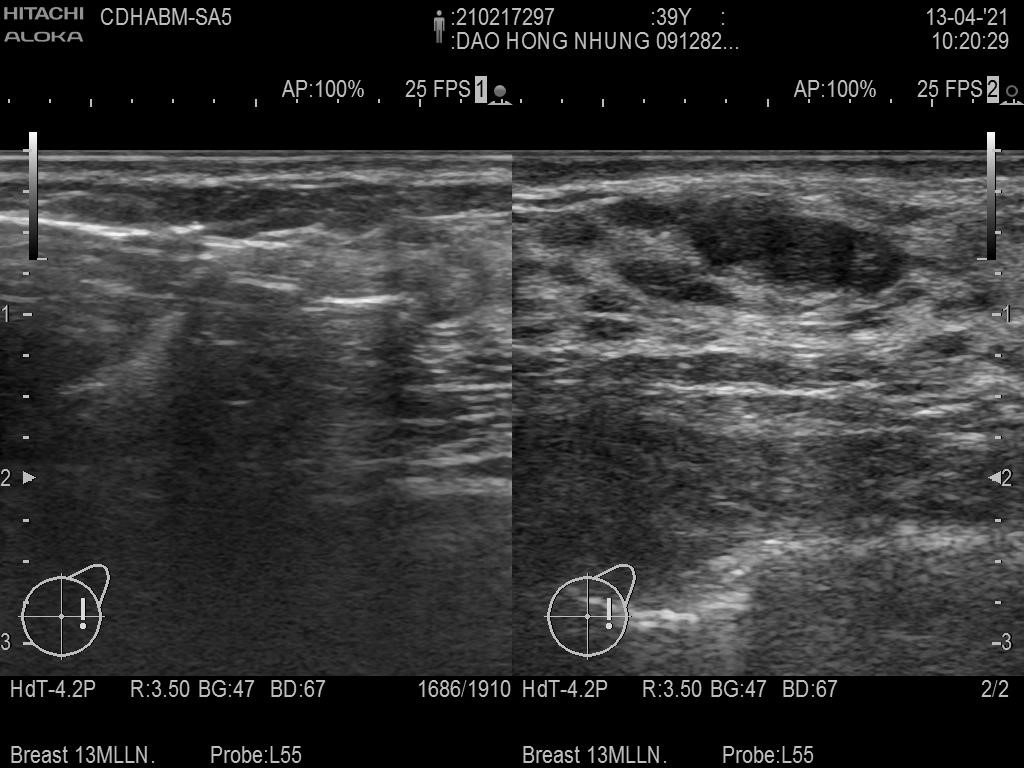

Ảnh phía trên là kim sử dụng hút chân không, chọc 1 lỗ rất nhỏ trên da để đưa kim tới tổn thương

Ảnh dưới bên phải: tổn thương khi chưa được hút (mũi tên chỉ vào tổn thương). Ảnh bên trái: sau khi hút bỏ tổn thương hoàn toàn (mũi tên chỉ vào kim hút chân không)